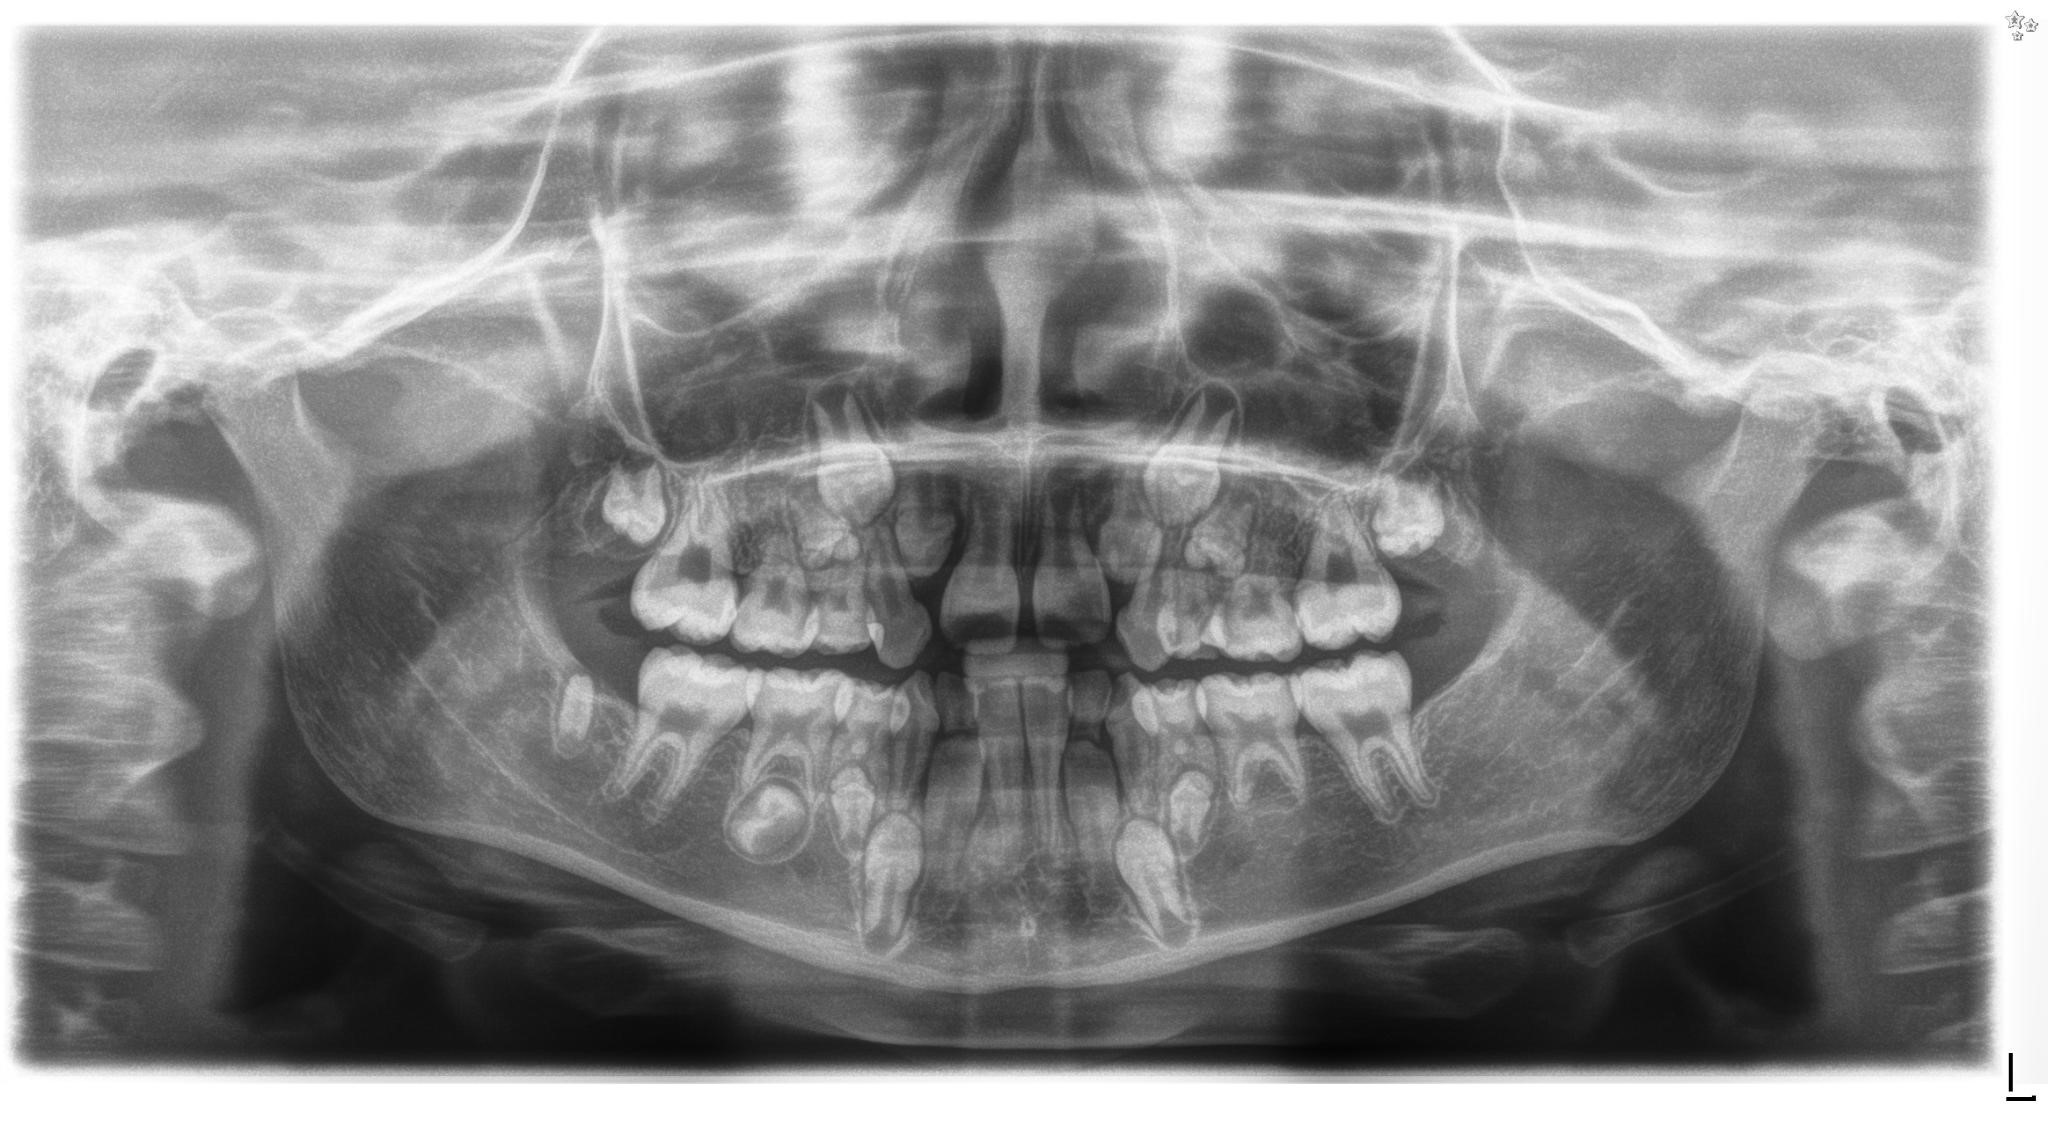

Figure 1. Panoramic radiograph of a 9-year-old girl treated for acute lymphoblastic leukaemia from the age of 15 months with subsequent 2 years of radiotherapy, chemotherapy, immunotherapy and antibiotic therapy, along with allogenic hematopoietic stem cell transplantation and two administrations of mesenchymal stem cells. Visible root shortening of all permanent first molar teeth, V-shaped roots of teeth 16 and 26, narrow roots of teeth 22, 36 and 46, absence of tooth buds 15, 25, 35 and 37, residual bud of tooth 47, microdontic buds of teeth 17, 14, 24, 27, 34 and 44 with disturbed mineralization (irregular crown outlines).